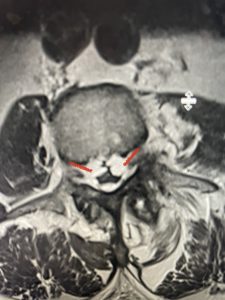

The next patient is a 71 year-old male with a two-year history of low back pain and lower extremity pain, numbness and weakness. His left leg was worse than the right. He had had five epidurals with no improvement. He also had tried physical therapy and medicines but nothing helped. He also felt that over the last three weeks he had gotten worse. He also had recently had some decreased sensation of bladder fullness and difficulty with bowel movements. MRI revealed a very tight L2-5 stenosis with an extruded L3-4 disc fragment (Fig 3).

(Figs 3a) Sagittal (a) and Axial (b) T2-weighted lumbar MRI demonstrating severe spinal stenosis L2-5 (arrow)and extruded disc at L3-4 on axial image (arrow)

He had concentric severe stenosis with severe compression of the lateral recess and foramen at L3-4 secondary to the superimposed disc herniation. The fact that he had gotten worse with subtle cauda equina features with an extremely tight canal, he underwent a decompressive laminectomy. We also augmented his laminectomy with an in situ fusion from L3-5 as he was relatively young, with more time to reform arthritis, and had been unstable enough to extrude a disc fragment. By placing “bone dust” or bone material along the sides of the spine, specifically laying it across the transverse processes after they have been drilled to bleeding bone, you provide an environment where bone formation is induced to connect the segments, stabilize them, and thereby reduce the signal to make more arthritis as that signal is still present despite the laminectomy. What was interesting was that we encountered a large extruded disk fragment that was significantly contributing to his compression which is often not found in patients in this age bracket. Post operatively he had much improvement of leg pain.